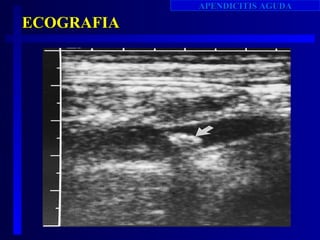

ECO ABDOMINAL

•Util pacientes sintomatología atipica.

•Realizada primera vez RG Leopold en 1981.

•Utilizan transductores de alta frecuencia( 5-7.5 MHz).

•Sensibilidad casi 100% en casos apendicitis obstructiva

•Menor apendicitis temprana.

•Reportes literatura:

sensibilidad: 76- 96%,

especificidad: 64-94%

precision Dx: 83-95%.

Charles S. Graffeo Emerg Med Clinics N A , Volume 14. Number 4. November 1996.

CRITERIOS ECOGRAFICOS

• la   visualizacion de un apendice no

comprimible con diametro mayor de 7 mm, es

el mas fuerte indicador de apendicitis .

•   Sensibilidad: 84%- 96%

•Especificidad: 94%-98%

Marshall E. Yacoe. Radiology Clinics of N.A. Vol 32 :5 sept 1994.

• Apendice mayor de 7mm en el diametro no compresible.

• Presencia de apendicolito.

• interrupcion de la continuidad ecografica de la submucosa.

• Demostracion ecografica de masa periapendicular o

coleccion de fluido

• Coleccion de liquido generalizada en el peritoneo que

sugiera perforacion